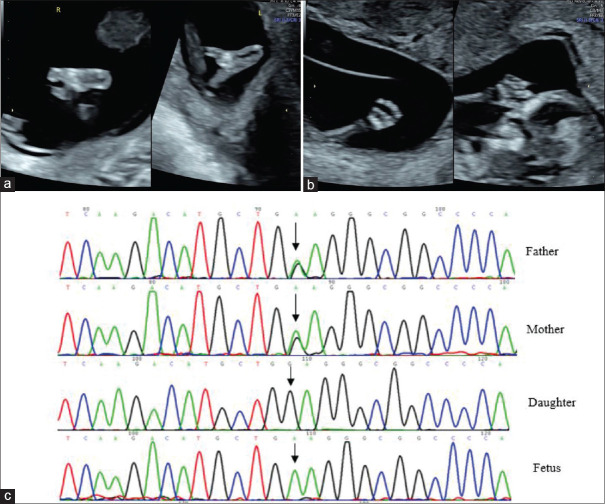

Early Prenatal Detection of Recessive Split-hand/Foot Malformation Caused by a Homozygous Variant of <i>WNT10B</i>.

Early Prenatal Detection of Recessive Split-hand/Foot Malformation Caused by a Homozygous Variant of WNT10B.